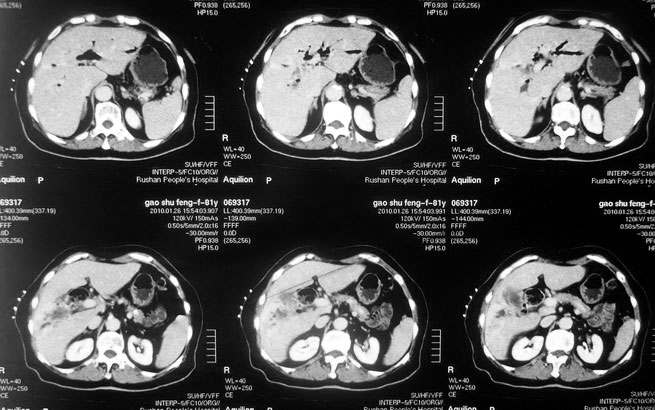

女,80岁既往有胆系手术史。近2月出现食欲不振,近20天出现畏寒发热,体重约下降10kg,体温一般在38℃左右。血常规wbc正常,中性比例88%,cea 10.3,afp、ca199均正常。做过一次肝穿,抽出约3ml仿佛脓性液体。这是她的增强ct扫描,请大家帮帮忙。另外想问问肝脓肿和胆管细胞癌的ct表现有什么区别。谢谢了。

【湘江一滴】化脓性胆囊炎及胆管炎,肝内胆管积气、积液、扩张;胆囊壁增厚、强化;胆周积液。未见肝内占位征象。

【shuiyuan】化脓性胆囊炎及胆管炎,肝内胆管积气、积液、扩张;胆囊壁增厚、强化;胆周积液.

肝脓肿动脉期呈明显环形强化或蜂窝状强化,胆管细胞癌动脉期强化不明显,且伴肝内胆管扩张。

【zenxisengming 】肝内胆管扩张积气,胆囊比环形增厚,胆囊周围渗出,未见占位性病变,应该是胆道化脓性感染

【sunbin】肝内见多个气体密度影伴气液面,胆囊壁增厚,胆囊周围低密度环绕,未见强化,支持化脓性胆管炎、胆囊炎。

最近复查ct,做了第二次穿刺抽脓,顺便做了涂片病理活检,结果找到恶性肿瘤细胞,诊断肝癌合并肝脓肿。看来大家都走眼了啊。